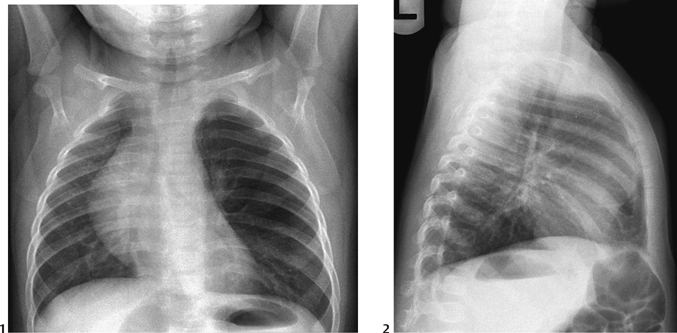

ENFISEMA LOBAR CONGENITO PDF  Congenital lobar emphysema | Radiology Case | Radiopaedia.org

Congenital lobar emphysema | Radiology Case | Radiopaedia.org  Lobar holoprosencephaly | Radiology Case | Radiopaedia.org

Lobar hemorrhage | Radiology Reference Article | Radiopaedia.org  Congenital Lobar Emphysema - The Clinical Advisor

Congenital Lobar Emphysema - The Clinical Advisor  Lobar Holoprosencephaly in 2020 | Retroverted uterus, Cleft lip and palate, Cleft lip

Congenital lobar overinflation | Radiology Reference Article | Radiopaedia.org  CONGENITAL LOBAR EMPHYSEMA | buyxraysonline

CONGENITAL LOBAR EMPHYSEMA | buyxraysonline  ENFISEMA LOBAR CONGENITO PDF

39 Congenital Lobar Emphysema | Radiology Key  Right upper lobe consolidation: an unusual complication of an uneventful endotracheal intubation

Congenital Lobar Emphysema Article  PPT - Chest X-Ray Interpretation for the Internist PowerPoint Presentation - ID:934924

Congenital Lobar Emphysema - Metabolic Disorders - My Fertility Guide  Congenital Lobar Emphysema | Thoracic Key

Congenital Lobar Emphysema | Thoracic Key  a CT showing large lobar hemorrhage at the left parietal lobe. b A | Download Scientific Diagram

Congenital lobar emphysema: diagnostic and therapeutic challenges | BMJ Case Reports  Lobar hemorrhage | MedLink Neurology